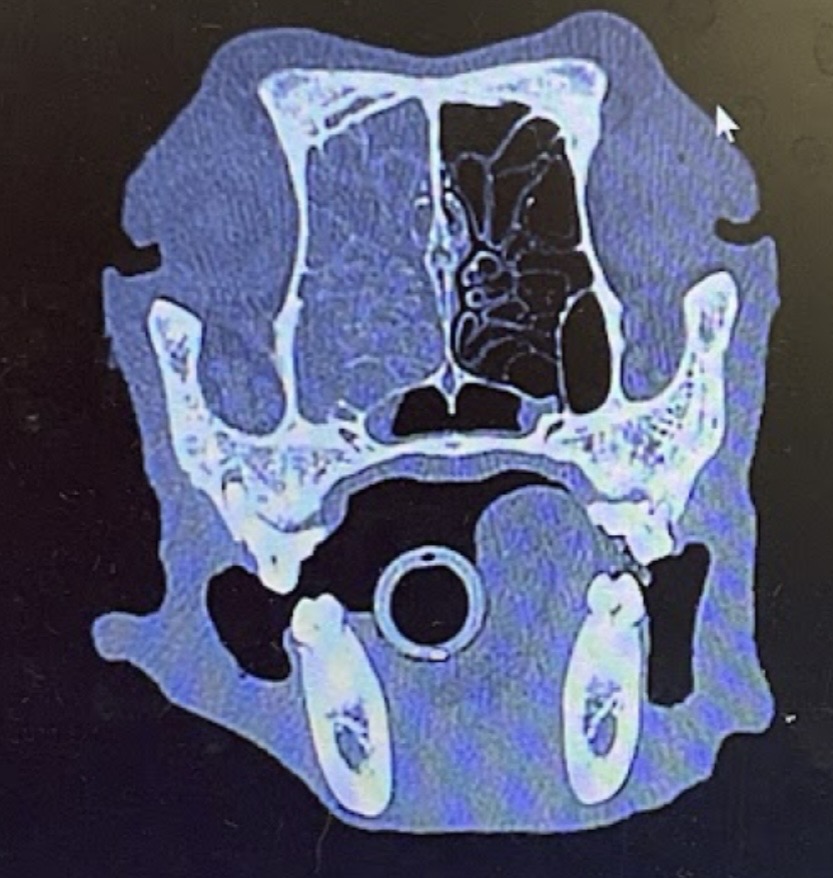

X線検査やCT、MRIといった高度画像診断は、腫瘍の浸潤範囲を正確に把握し、治療法を計画し、そして予後を予測するために不可欠なプロセスです。

| CT検査 | 標準的検査法。骨破壊の評価、腫瘍の三次元的範囲の特定、放射線治療計画 | 高い空間分解能、骨構造の極めて詳細な描出、迅速な撮像 | 軟部組織のコントラストがMRIに劣る、腫瘍と炎症・液体の識別が困難、放射線被曝 |

犬の鼻腔内腫瘍において、最も重要かつ決定的な意味を持つのが、CT検査で評価される篩板(しばん)への浸潤の有無です。篩板の破壊は、腫瘍が頭蓋内へ浸潤していることを意味し、予後が統計学的に有意に悪いことが一貫して報告されています。

獣医師が飼い主と治療方針について話し合う際、CT画像における篩板の状態は、議論の中心に据えられるべき最も重要な情報です。篩板が「保たれている」か「破壊されている」かという所見が、その後のケアの方向性と飼い主の心構えの全てを決定づけるのです。